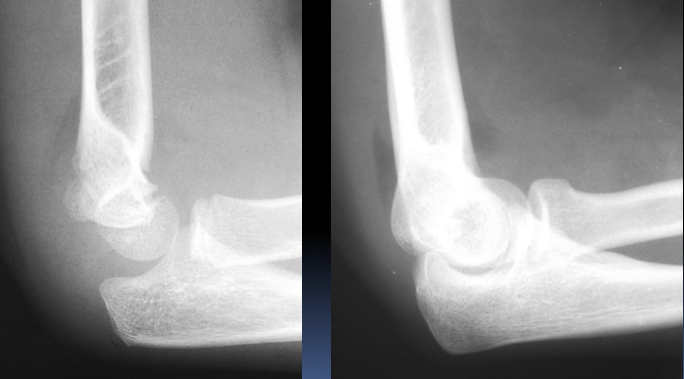

More subtle supracondylar fracture x-rays.

What are elbow fat pads?

A potential finding on elbow radiography which suggests a fracture of one or more bones at the elbow:

Which elbow fat pads are visible on an x-ray?

Often the small anterior fat pad can be seen on a normal lateral elbow x-ray

The posterior fat pad is never visible on a normal xray

What is an intraarticular fracture? How can it present on an x-ray?

A fracture inside the joint capsule - can cause bleeding and swelling inside the capsule

This pushes up against the fat pads and pushes them away from the humerus - become more visible on x-rays as dark grey areas anterior and posterior to the joint